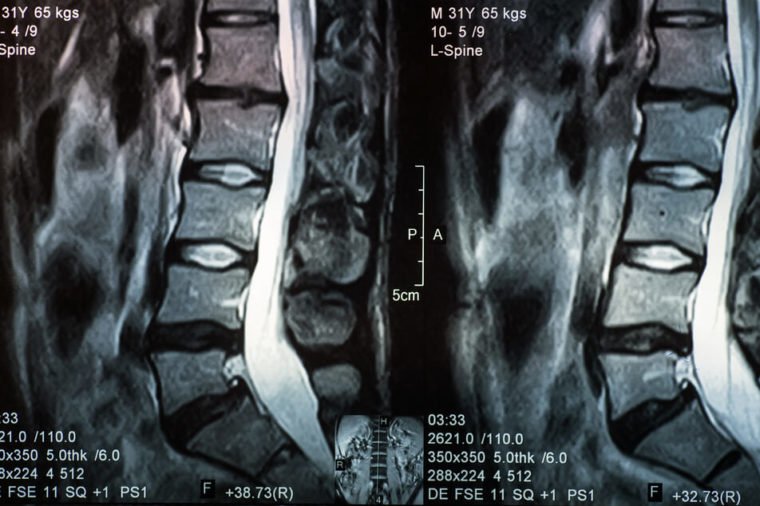

From too-high heels to poor nutrition, your back can start aching for any number of reasons. Sometimes, when the shock-absorbing discs in your vertebrae herniate or rupture, their gel-like center can press up against and irritate surrounding nerves. The result? You may feel significant pain. However, that’s not a guarantee—many people don’t have any symptoms, or their herniated disc symptoms could be masquerading as something else.